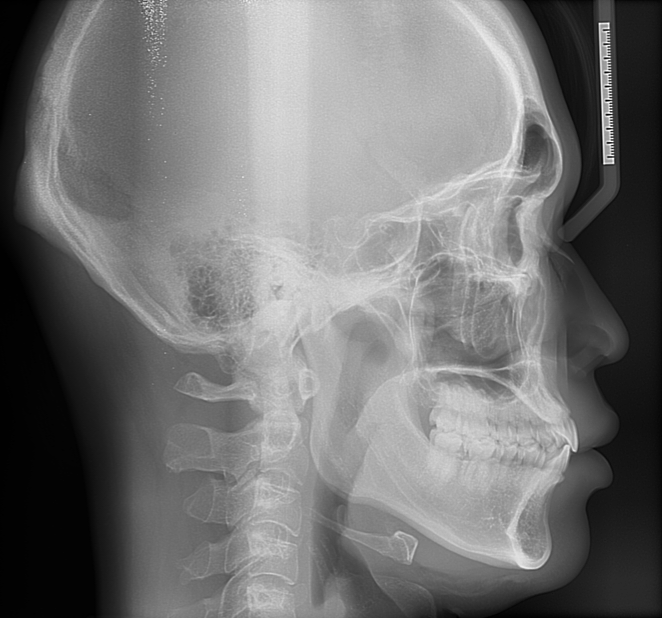

치아 돌출입 일까요? 골격돌출입인가요?